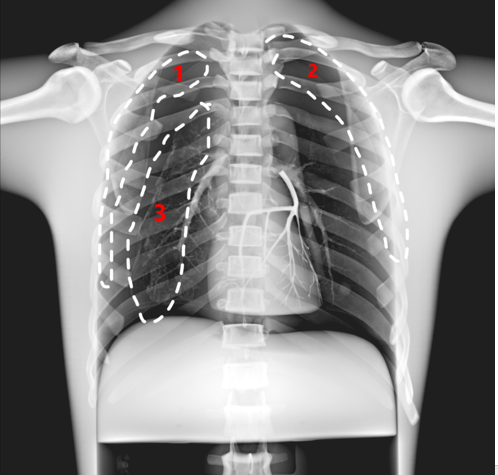

1和2肺部軟組織陰影 3肺炎斑塊

2. 5種標(biāo)準(zhǔn)病理學(xué)形態(tài)模擬

1)第一左肋尖端上2個(gè)連續(xù)的直徑0.5cm結(jié)節(jié)

2)疊加在左肺下葉大血管上的直徑0.6cm結(jié)節(jié)

3)左縱膈陰影區(qū)直徑1.5cm結(jié)節(jié)

4)混合在右肺動(dòng)脈0.6cm結(jié)節(jié)

5)右下肺葉肺炎模擬